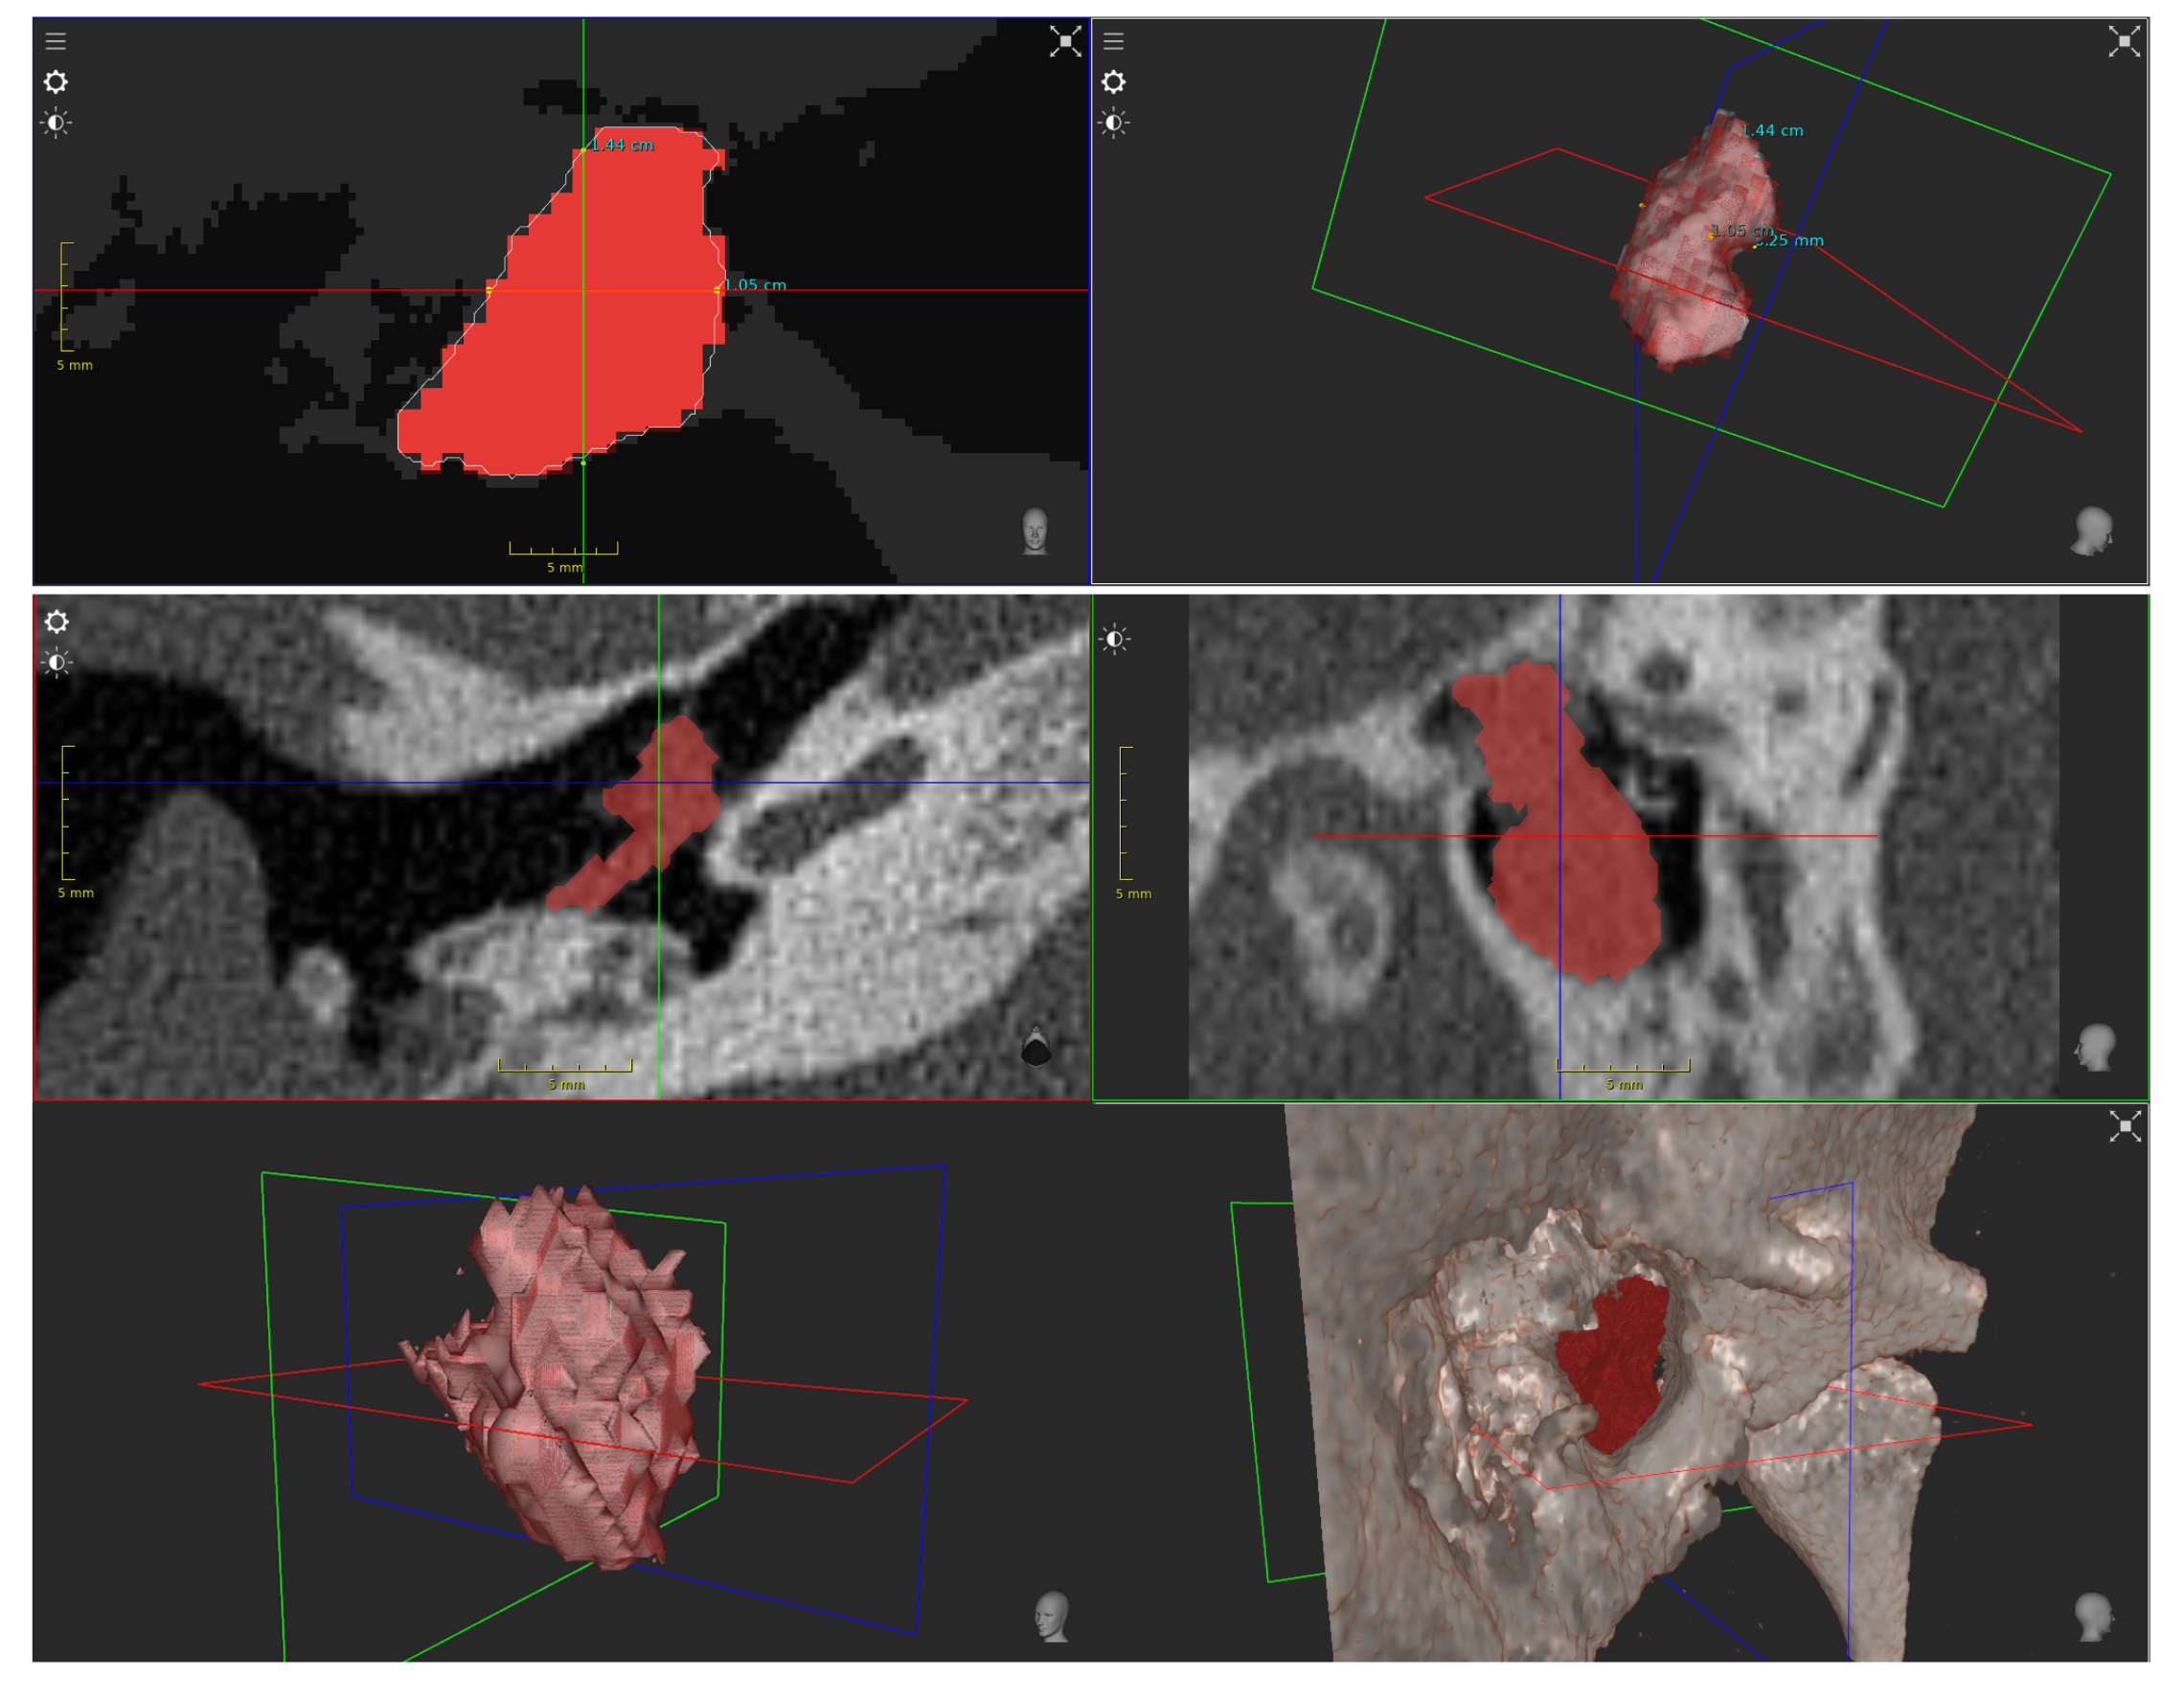

3.3. Multispectral Stereo Acquisition